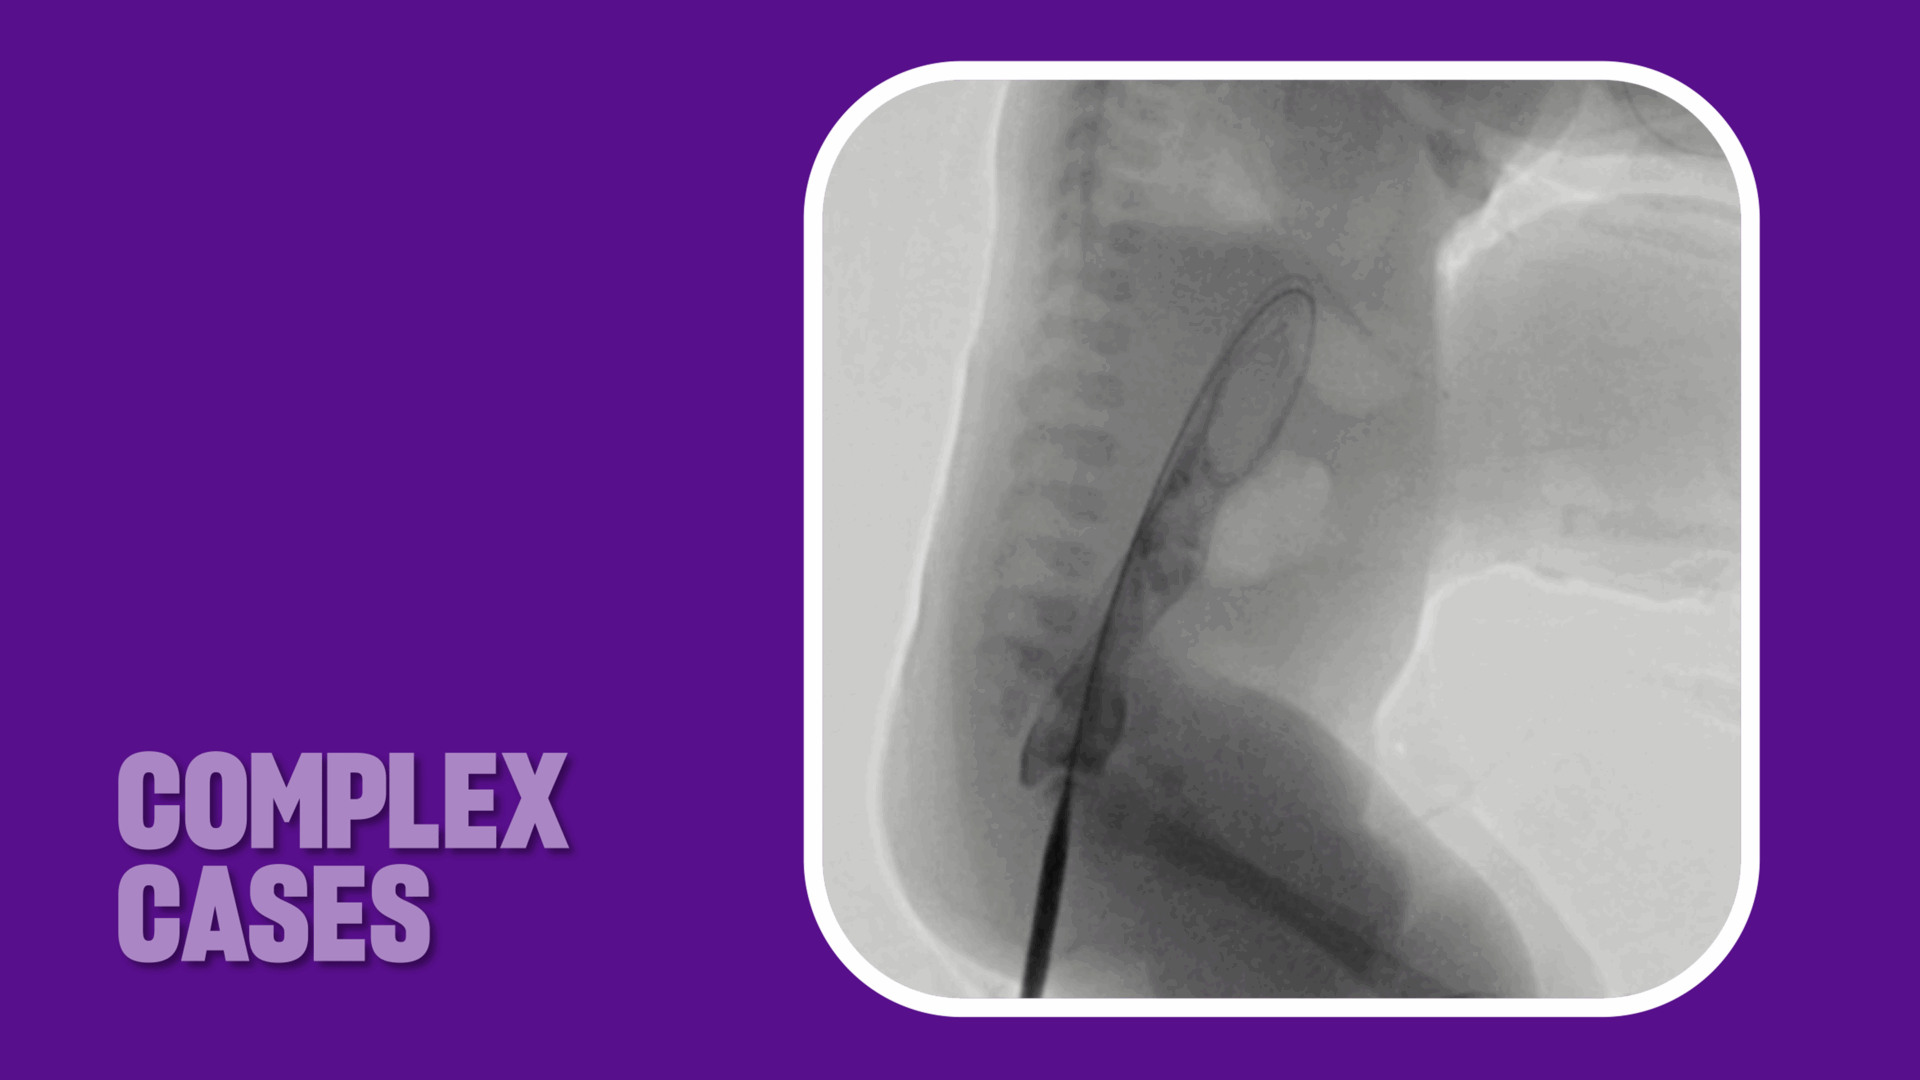

Over a period of six weeks, the team progressively dilated the neo-anorectal tract under fluoroscopic guidance. “It was a nice combination of skill sets and we had regular conversations about when to safely upsize the tract and how to manage it exactly,” Dr. Bertino says. “So it was a good long-term collaboration.”

Seldinger technique allowed for serial dilation of the neo-anorectal tract under fluoroscopic guidance. Source: NYU Langone Health.

Inserting a stiff wire through the neo-anorectal tract allowed for serial dilation of the tract under fluoroscopic guidance. Source: NYU Langone Health.